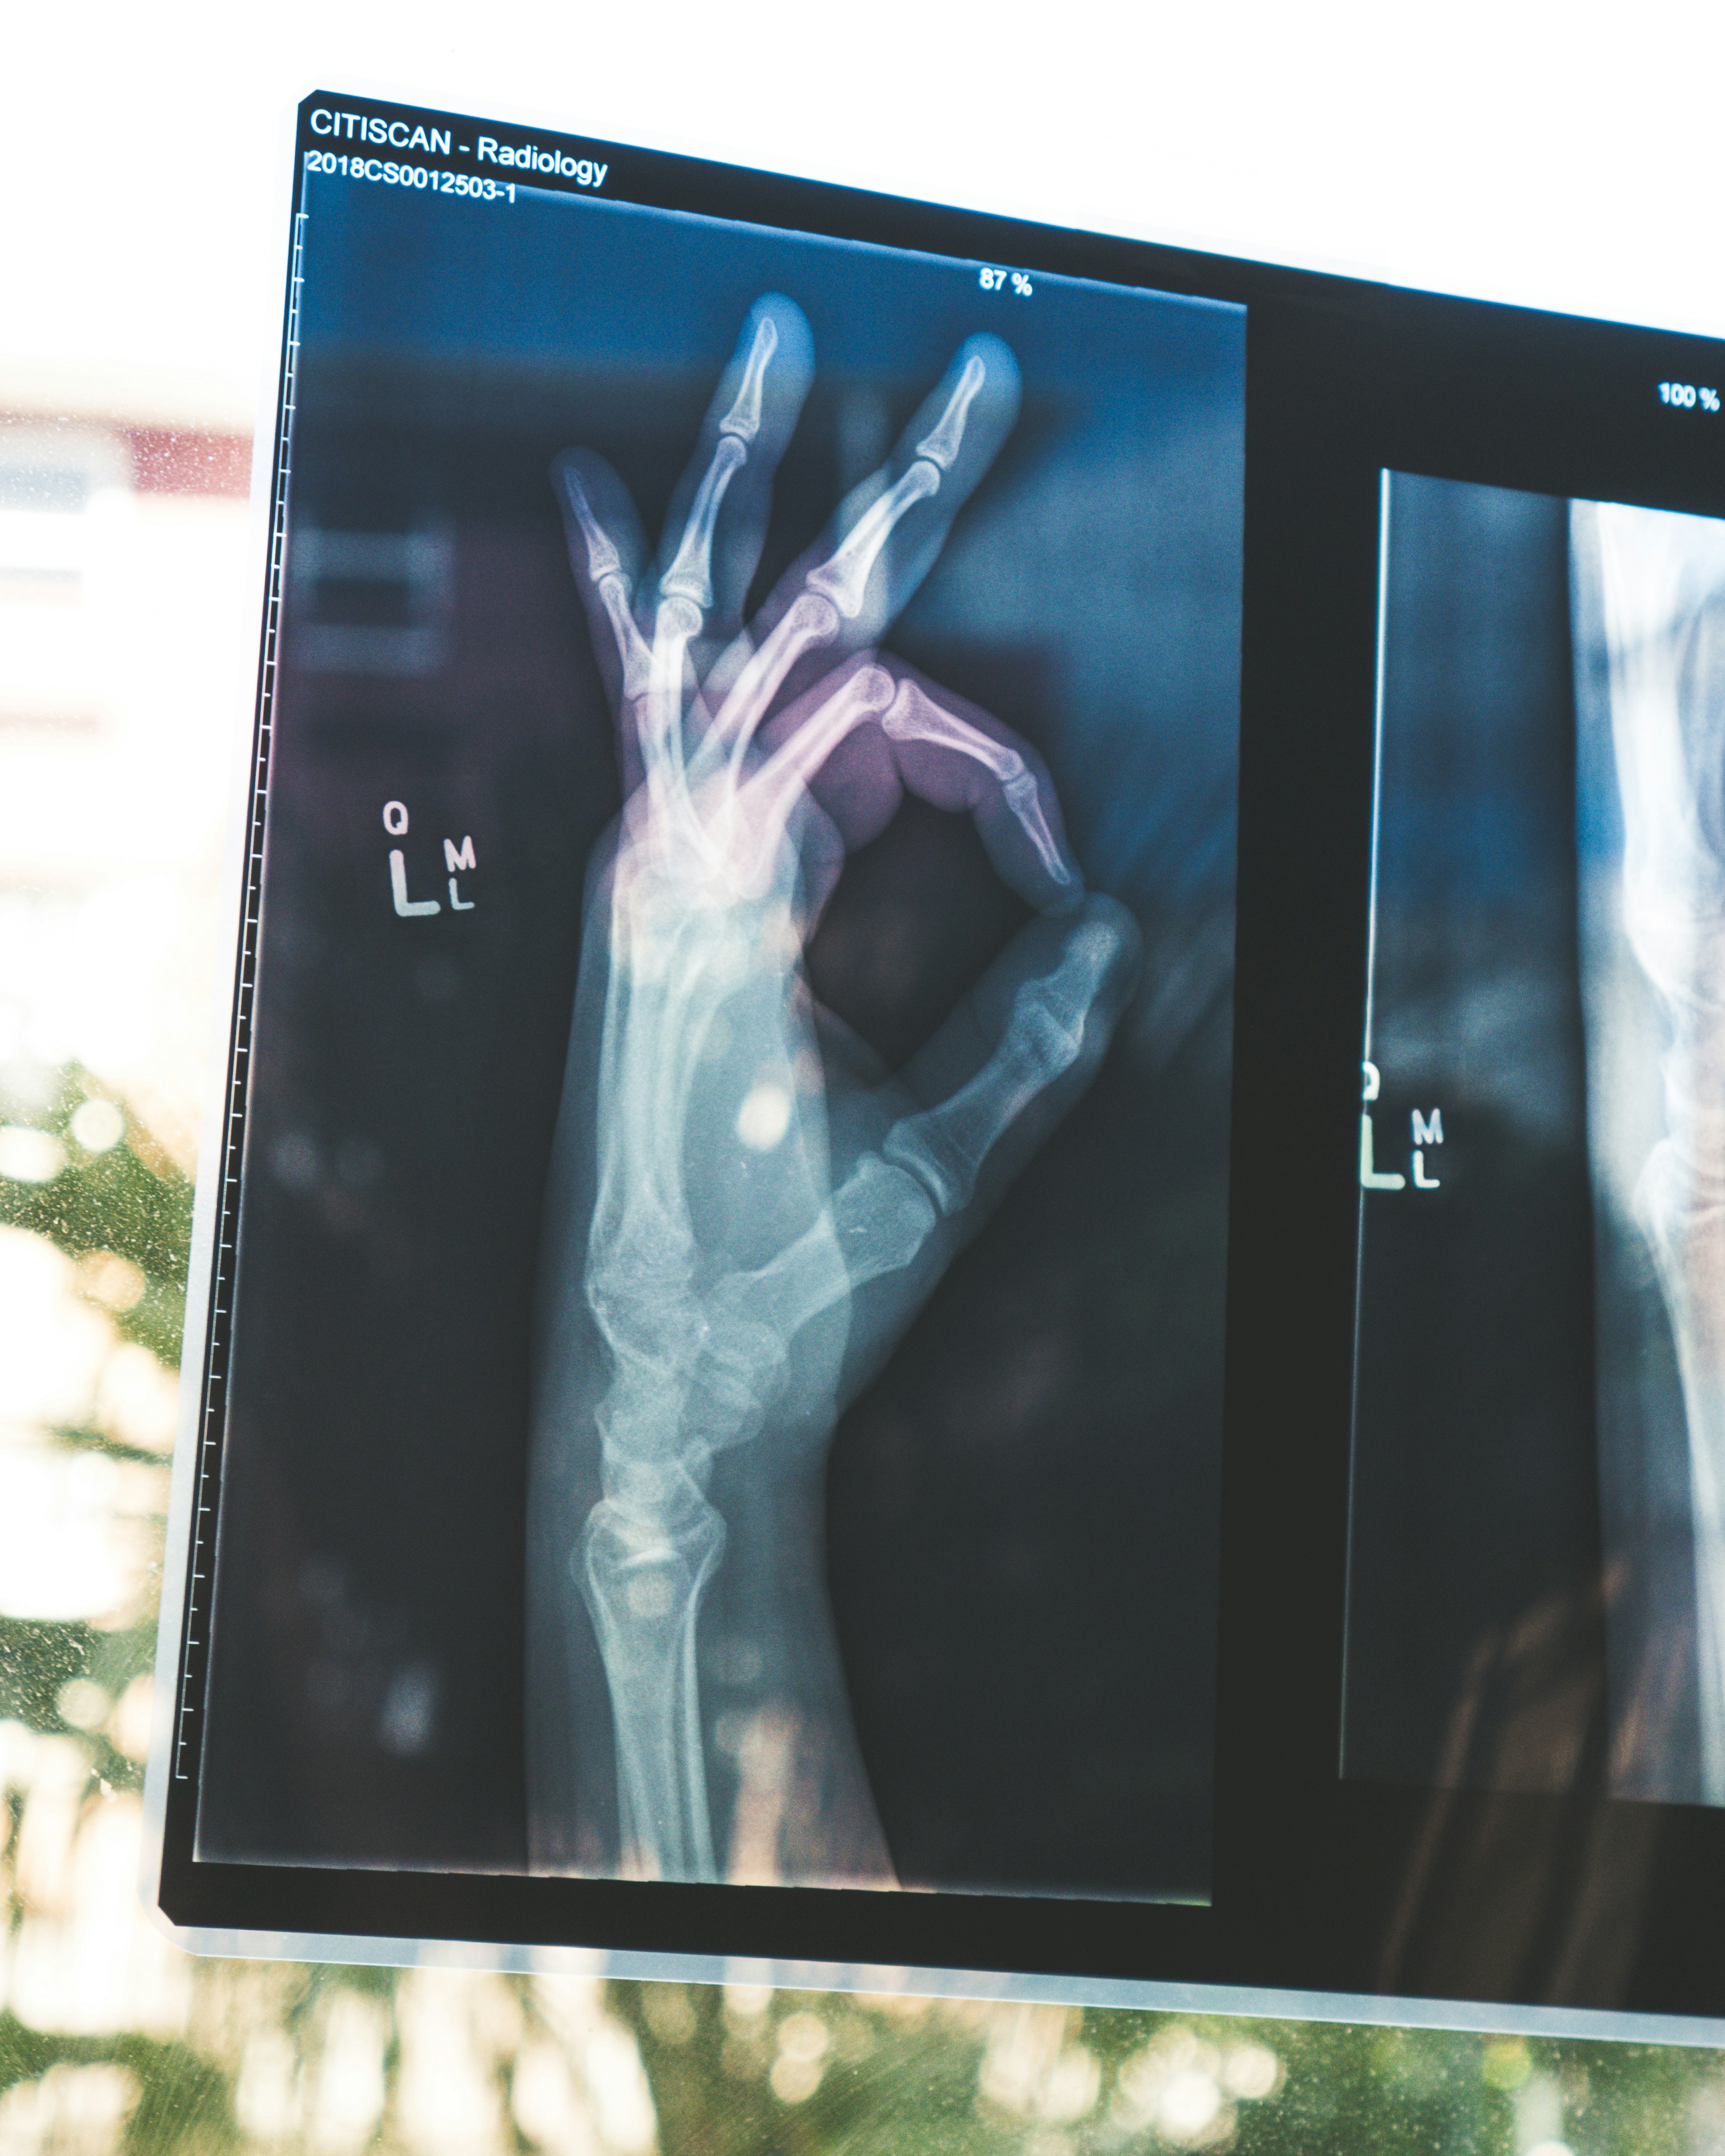

제가 처음 내시경을 받았을 때, 의사 선생님은 위의 특정 부위가 창백하게 보이고, 점막이 매끈하지 않다고 하셨습니다. 조직검사 결과지에서 ‘intestinal metaplasia(장상피화생)’라는 단어를 확인하고 나서야 비로소 확실하게 이해할 수 있었죠. 의사 선생님께서는 “이 상태가 당장 암은 아니지만, 장기간 방치되면 암으로 발전할 수 있다”고 설명하셨습니다.

- 내시경으로 위 점막 상태 확인

- 조직검사를 통한 확정 진단